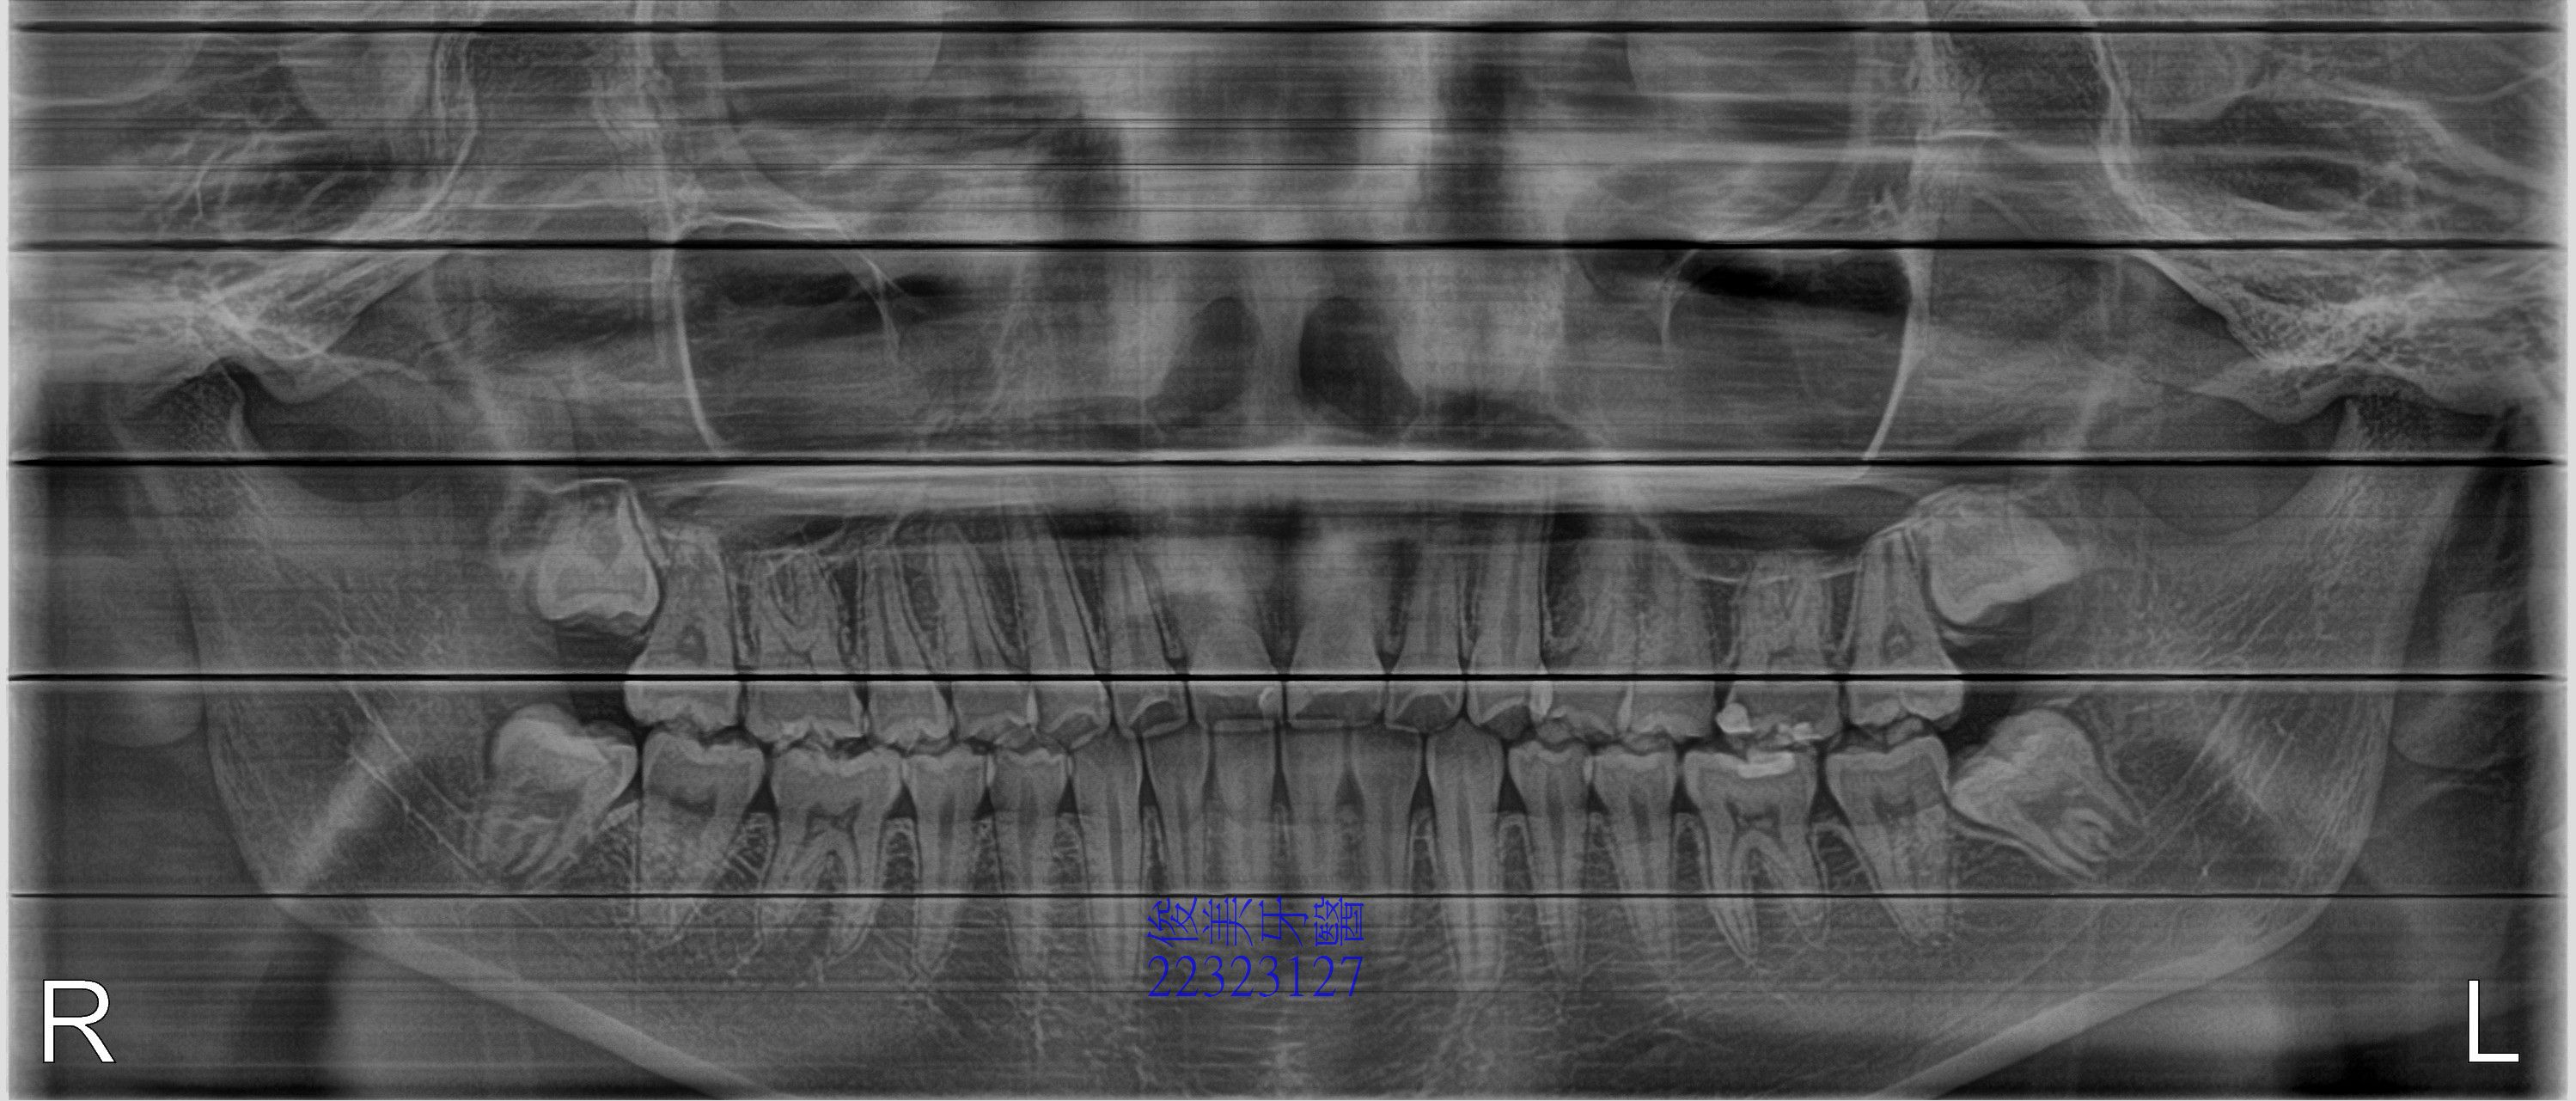

埋伏智齒拔牙案例8

患者因已18歲,担心自己有智齒需處理,經朋友介紹來就診檢查,果然由x光發現,共有4顆智齒阻生智齒,

為避免將其他牙齒推歪,患者當下就決定先拔除一顆。

醫師建議先將上顎智齒拔除,再依次拔除下顎智齒。